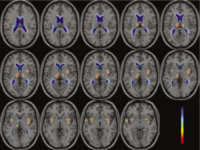

Neural Substrates of Working Memory in SchizophreniaThis project assesses working memory using an auditory verbal version of the n-back task paradigm. Three conditions are presented in blocks in counterbalanced order with increasing working memory load demands (0-, 1-, 2- and 3-back). More... New: December 20, 2005: Marek Kubicki visit to Dartmouth. | |

Brain Activation during Continuous Verbal Encoding and Recognition Task in SchizophreniaThis project employs an event-related auditory verbal episodic memory probe targeting medial temporal and DLPFC circuitry. The task uses a continuous performance format where concrete nouns are presented initially as new items. Words are then repeated after short or long intervals and the participant is required to make a new/old distinction. This design permits analysis of both encoding and recognition processes. More... New: December 20, 2005: Marek Kubicki visit to Dartmouth. |